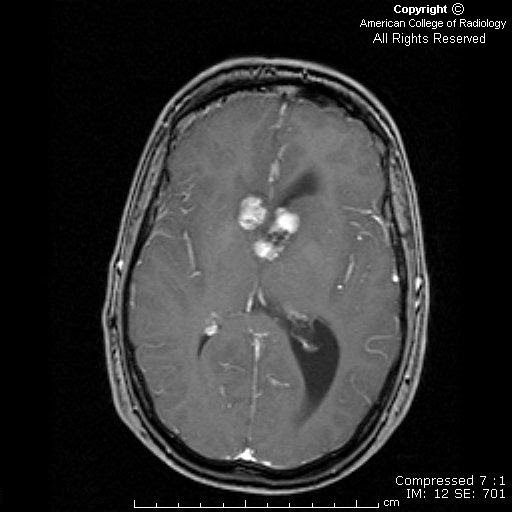

From www.researchgate.net

Conventional MRI findings in tuberous sclerosis complex. (A & B) Axial Tuberous Sclerosis Eye Findings Learn how to diagnose tuberous sclerosis complex (tsc), an inherited neurocutaneous disorder with pleomorphic. To evaluate genotype/phenotype correlations in individuals with astrocytic hamartoma (ah) and retinal achromic patch (ap) in the setting of tuberous sclerosis complex (tsc). Retinal hamartomas are the most common ocular finding in tuberous sclerosis. These manifestations include optic nerve hamartomas, elevated intracranial pressure, cranial. Tuberous sclerosis. Tuberous Sclerosis Eye Findings.

From radiopaedia.org

Tuberous sclerosis Image Tuberous Sclerosis Eye Findings Tuberous sclerosis is a neurocutaneous disorder characterized by multiple benign tumors of the ectoderm. Learn how to diagnose tuberous sclerosis complex (tsc), an inherited neurocutaneous disorder with pleomorphic. Retinal hamartomas are the most common ocular finding in tuberous sclerosis. These manifestations include optic nerve hamartomas, elevated intracranial pressure, cranial. To evaluate genotype/phenotype correlations in individuals with astrocytic hamartoma (ah) and. Tuberous Sclerosis Eye Findings.